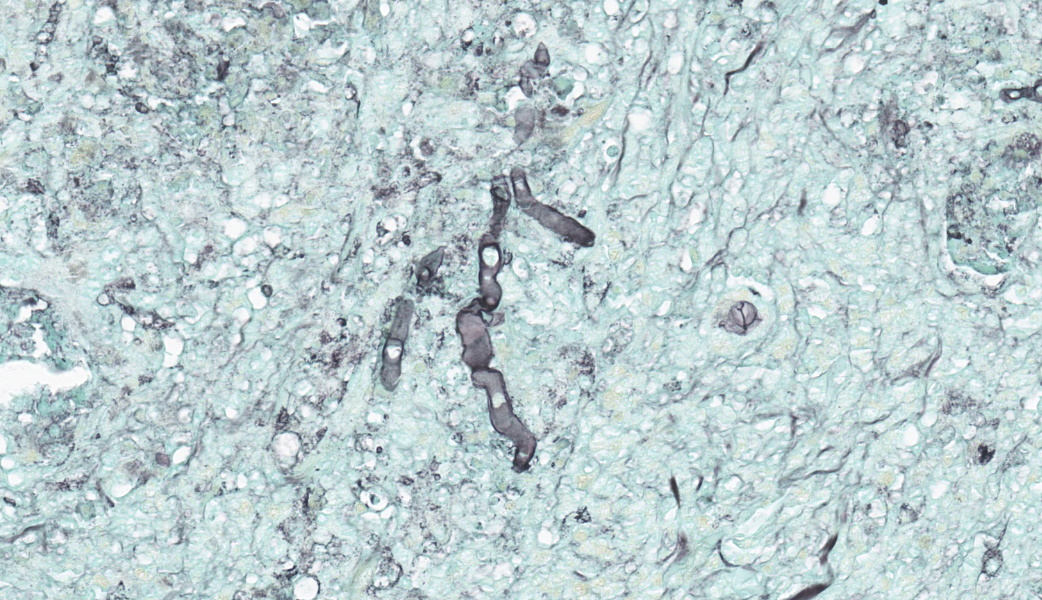

Brain, right frontal lobe: the leptomeninges are focally extensive and moderately expanded by pyogranulomatous exudate. The exudate is formed by nodular to coalescent (mild slide variation) collections of epithelioid macrophages, lesser eosinophils, lymphocytes and plasma cells and few Langhans giant cells. The granulomatous component is admixed with plump fibroblasts, thin bundles of fibrous tissue, and multifocal aggregates of granular, deep basophilic and dense material (mineral). Among the cell debris or in the cytoplasm of the multinucleated cells there are tubularly elongated (when longitudinally sectioned), circular or oval (when transversally sectioned) structures barely stained and hard to visualize in hematoxylin and eosin (HE) stained slide ("negative" images of fungal hyphae). The hyphae are characterized by a body that is hollow or filled with eosinophilic or basophilic granular material and surrounded by varying, but mostly scarce, amounts of strongly eosinophilic, smooth or granular material (Splendore-Hoeppli reaction). The wall of medium-sized arteries in the affected areas is segmentally or cincunferentially expanded by acellular, bright eosinophilic and homogeneous material (fibrinoid necrosis) and occasionally there are hyphae infiltrating the vessel wall or associated with thrombosis in the vessel lumen. There is a focally extensive area of necrosis of liquefaction, swelling of astrocytes and cavitation of nervous tissue, where the parenchyma has been replaced by proliferating microglial cells, many of which already differentiate into foamy macrophages (gitter cells). Perivascular cuffs containing up to three layers of lymphocytes are also observed. The organisms stain well by the GMS method as slightly branched hyphae with an irregular diameter of 7-10 μm, associated with foci of necrosis. Occasionally there is a rounded structure of larger diameter (up to approximately 15 μm) at the end of the hyphae.Lung: there are focal to coalescent areas of consolidation consisting of nodules or sheets of large numbers of epithelioid macrophages and Langhans giant cells admixed with numerous eosinophils and surrounded by fibroblasts and fibrous tissue. The macrophages encircle hyphae similar to that described in the brain that are surrounded by moderate to abundant Splendore-Hoeppli material. Throughout the lung parenchyma there are also small multifocal areas of necrosis containing hyphae. Mineralization is sparsely observed amid necrosis and inflammation. Diffusely, the reminiscent alveolar septa are mildly infiltrated by neutrophils and eosinophils.

Brain, pyogranulomatous meningoencephalitis, focally extensive, with fibrinoid vasculitis and trombi, associated with intralesional fungal hyphae, morphology consistent with Conidiobolus sp.Lung, pyogranulomatous pneumonia, multifocal to coalescent, associated with intralesional fungal hyphae, morphology consistent with Conidiobolus sp.

Discussion focused on indicative features of a zygomycete histologically, which include a broad diameter ranging from 5-15um, non-parallel thin walls, rare septations, asymmetric acute-angle branching, and potentially a terminal bulb. Zygomycetes are typically weakly PAS-positive and more strongly GMS-positive. This correlated nicely with the PAS and GMS stains run in-house. Other differentials mirrored those discussed by the contributor, including oomycetes like Pythium insidiosum, which would be PAS-negative and GMS-positive, as well as Basidiobolus spp., another member of the Entomophthoramycota family alongside Conidiobolus. However, Basidiobolus spp. typically affect the thorax, trunk, limbs, intestinal tract, and, in atypical cases, can cause systemic infection.28Conidiobolus is far more commonly seen localized to face and nostrils. Using a variety of proteases (including elastase and collagenase), lipases, esterases, and glycoside hydrolases at their disposal, Conidiobolus spp. can wreak havoc to the nasal and facial bones and surrounding soft tissues24. Ultimately, they may eat through the cribriform plate and enter the brain.28,29 It’s pretty much “game over” at that point.